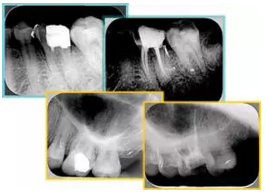

共有 4 張 X 線片,分別是術(shù)前、診斷絲 、主牙膠尖確認(rèn)、術(shù)后。

( 1 )術(shù)前:術(shù)前 X 線片用來了解牙齒的大概情況。術(shù)前預(yù)期為多根牙時 X 線片應(yīng)偏頭拍攝。

( 2 )診斷絲:根據(jù)術(shù)前 X 線片進(jìn)行開髓、根管的初步預(yù)備后,需要插入診斷絲,用來指示工作器械位置。常用 10 號或 15 號擴(kuò)大器作為診斷絲插入牙髓腔。

( 3 )主牙膠尖確認(rèn):通過術(shù)前預(yù)期和診斷絲診斷,明確工作長度、牙根走向,進(jìn)行根管預(yù)備。之后應(yīng)進(jìn)行主牙膠尖(中銼)確認(rèn),已明確根管是否適合充填。

( 4 )術(shù)后:觀察治療效果。

6. 術(shù)后 X 線片

術(shù)后 X 線片用來評定根管充填 長度、致密度(管壁清晰、側(cè)枝)等指標(biāo)。

圖為根管充填術(shù)后 X 線片。圖中可見,根管充填較好。右下圖有白色小點(diǎn),為側(cè)方加壓導(dǎo)致糊劑擠出所致,表明根管充填比較致密。